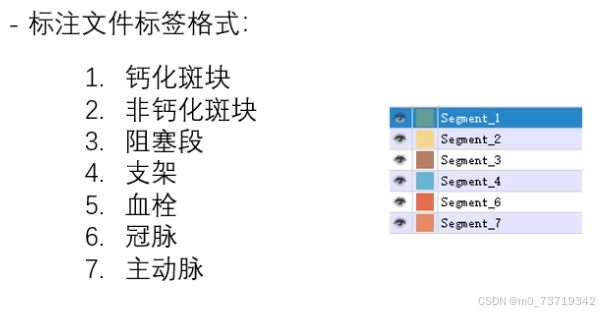

网络分割标签顺序(颜色无影响)